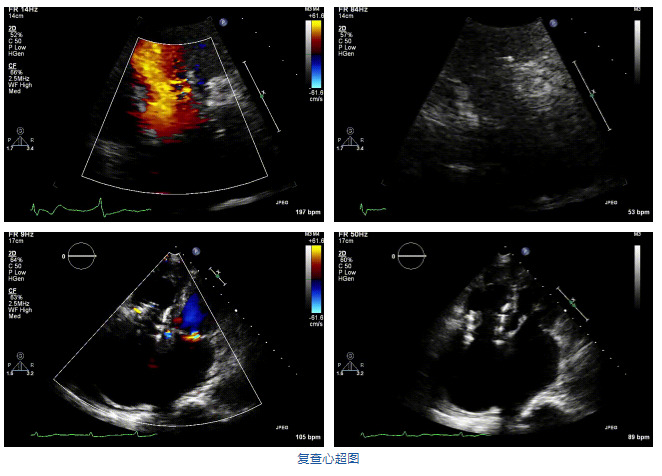

2021年12月7日,復旦大學附屬中山醫院葛均波院士團隊完成的首批兩例LuX-Valve Plus經血管三尖瓣置換患者順利出院,從患者入院至出院僅歷時一周時間,出院時患者狀態恢復良好,復查心超三尖瓣無反流。

結合術前CT評估結果,葛均波院士團隊最終決定選用LuX-Valve Plus 50mm和55mm兩種型號的瓣膜,并于2021年11月30日順利完成LuX-Valve Plus經血管三尖瓣置換術,手術室即刻拔除氣管插管,術后第二天轉出心內科監護室,下床活動。術后患者三尖瓣反流癥狀得到顯著改善,復查心超結果顯示人工三尖瓣瓣膜支架固定穩定,瓣葉關閉形態未見異常,未見明顯反流。

在本次救治性臨床研究中,治療的兩例患者病因不同,解剖結構復雜,均為極重度三尖瓣反流,手術最終都順利植入了LuX-Valve Plus三尖瓣人工瓣膜。術后超聲顯示瓣膜支架固定穩定,反流癥狀顯著改善,取得了良好臨床治療效果。